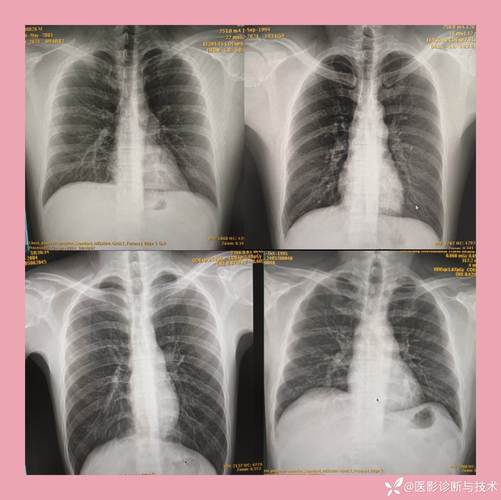

当医生在X光片上看到这个肺动脉段的弧度变得异常圆钝、饱满,甚至形成一个凸出的角度时,就称为“肺动脉段突出”,这本身不是一个疾病,而是一个影像学上的体征,它提示我们可能存在某些病理情况。

肺动脉段突出是右心室压力负荷增加或血流量增加的一个X线表现。

这种血流动力学变化直接反映在X光片上,就是肺动脉血流量增加导致其主干扩张,从而在X光片上表现为“肺动脉段突出”。

常见的具体疾病包括: